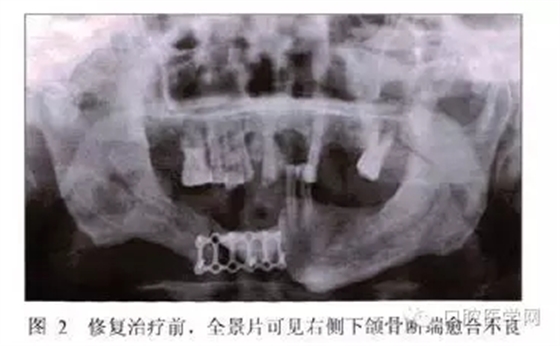

全景片示:下頜骨右側有不透光骨固定物,斷端結合處有透光影,余留牙處略有骨吸收,根尖周未見明顯異常(圖2)。